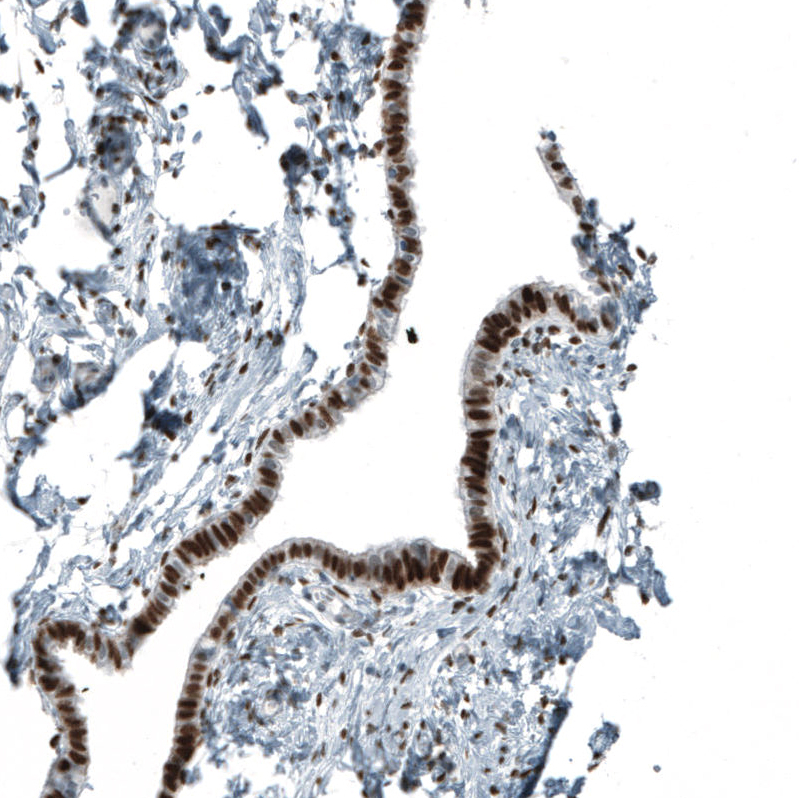

Immunohistochemistry analysis in human fallopian tube and cerebral cortex tissues using AMAb91547 antibody. Corresponding AR RNA-seq data are presented for the same tissues.